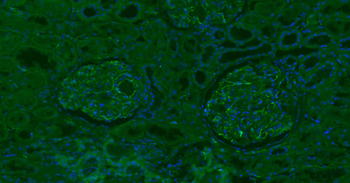

IHC-P image of mouse kidney tissue using CD31 antibody (dilution of primary antibody at 1:500)